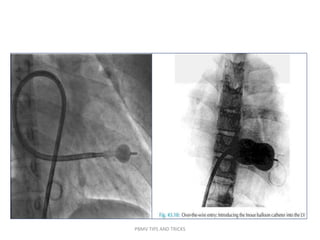

The goal of trans-septal catheterization is to cross from the RA to the LA through the fossa ovalis

The FO is located superiorly and posteriorly to the ostium of the CS and well posterior of

the TA and rRAA. The fossa ovalis is posterior and caudal to the aortic root and anterior to

the free wall of the right atrium